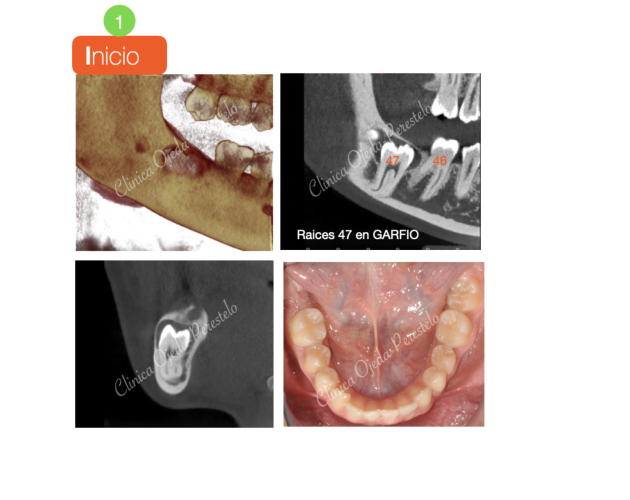

2ºMolar Mandibular Retenido Casos de Éxito - Dientes Retenidos